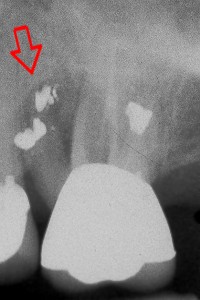

![]() The dark shadow around the root of this tooth indicates a tooth abscess or infection |

Tooth Root Amputation - Without Extracting the tooth!

If the proper conditions exist, we can section and extract the problematic root of a tooth, keeping the rest of the tooth intact! This patient fractured one of the 3 roots of an upper molar and elected to have the problem root removed. The tooth was then smoothed and a filling placed. The white spots at the ends of the roots represent fillings from a prior procedure called an 'apical retrofill'.